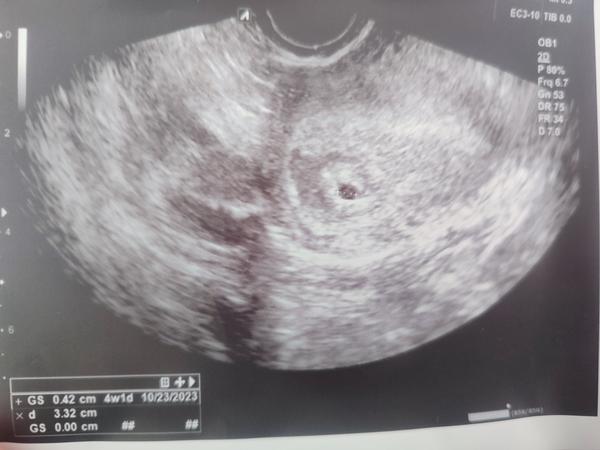

@anjelicek26 ahoj , chcela by som sa ťa aj ja opýtať ak nevadí , vyzerá že sa ozaj rozumieš tak len tvoj pohľad na vec.Ja mám cyklus 27-31 dní.Na 27 deň cyklu mi už clearblue ukázal 1-2 týždne. Ostatné testy ukazovali slabého ducha...týždeň na to už boli aj na ostatných testoch koľajnice.Včera som bola na prvej kontrole -41DC , kedy som mala byť podľa poslednej ms 5+6. Na ultrazvuku ale bol vidieť len malý gestačný vak ....nič iné .Ako som sa pozrela na sono obrázok, tak nález zodpovedá týždňu 4+1. Lekár hovoril že to je úplne normálne , objednal ma o tri týždne ale mne sa to nezdá , keďže pozitívny test mi vyšiel už dva týždne pred kontrolou.Myslíš že je ešte šanca ? 🙏 Ďakujem krásne